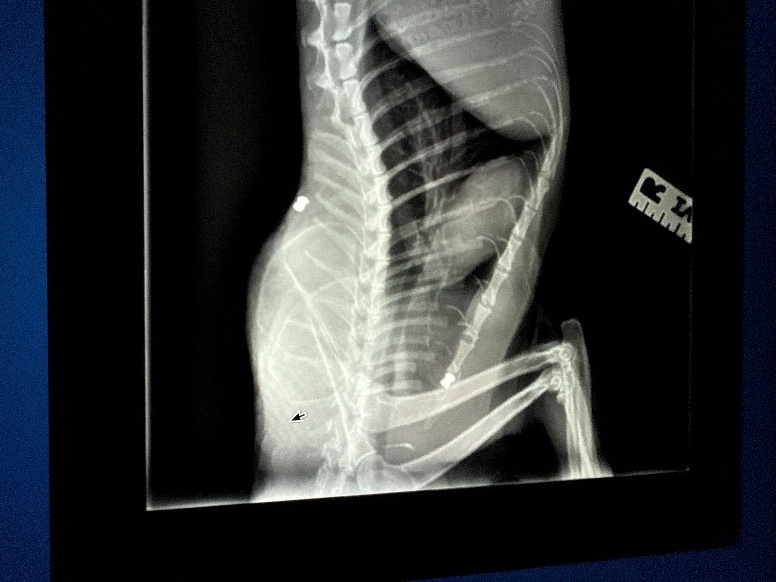

X-ray of the second cat found recently near West 94th Street and Vermont Avenue, showing the bullet permanently lodged in his back.

Credit: Friends of Normie